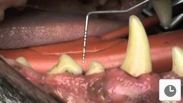

Dog With Severe Periodontitis

A dog with severe periodontitis is examined by Andrew Perry BVSc MRCVS on our YouTube channel.